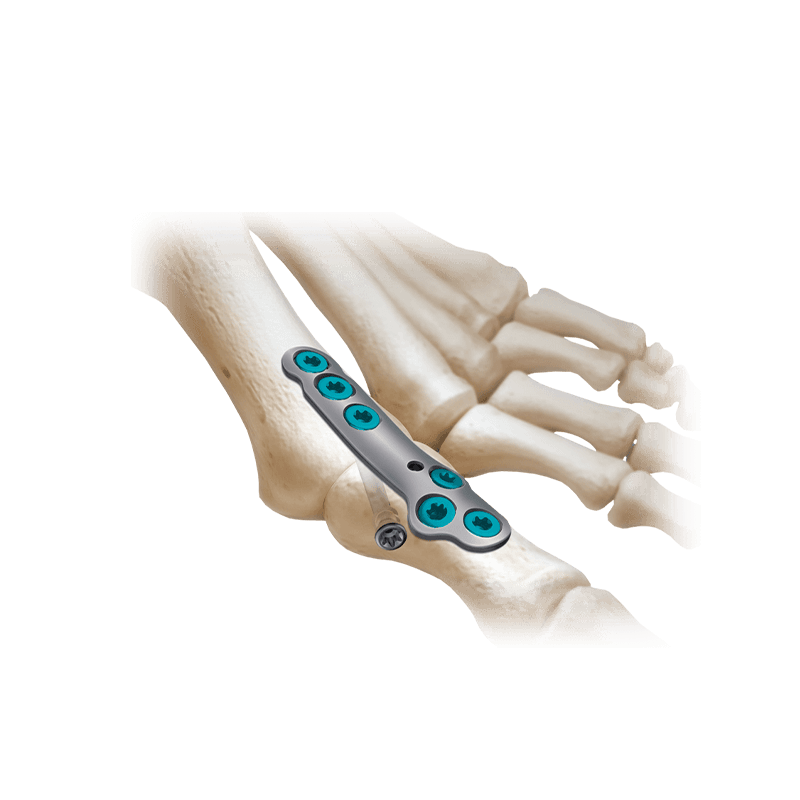

Plating Systems & Compression Hardware

Plating Systems & Compression Hardware

Plating systems and compression hardware for forefoot procedures.

Fixation Devices - Plating Systems

CoLink® NX MTP Compression Plating System

Featuring an elliptical slot with progressive depth that aids mechanical compression